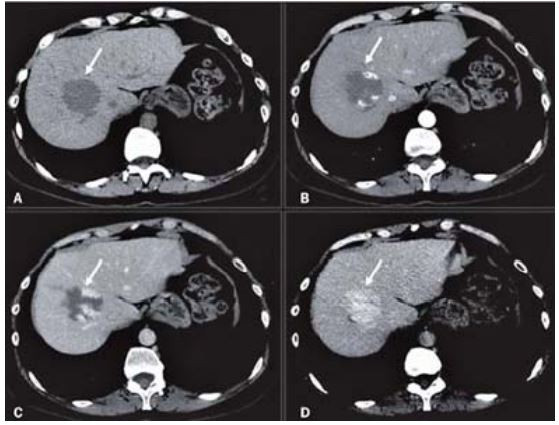

Os cortes abaixo são de uma tomografia computadorizada com contraste para avaliação de uma lesão focal hepática. Analise as imagens e marque a afirmação correta sobre a lesão focal encontrada.

Provas